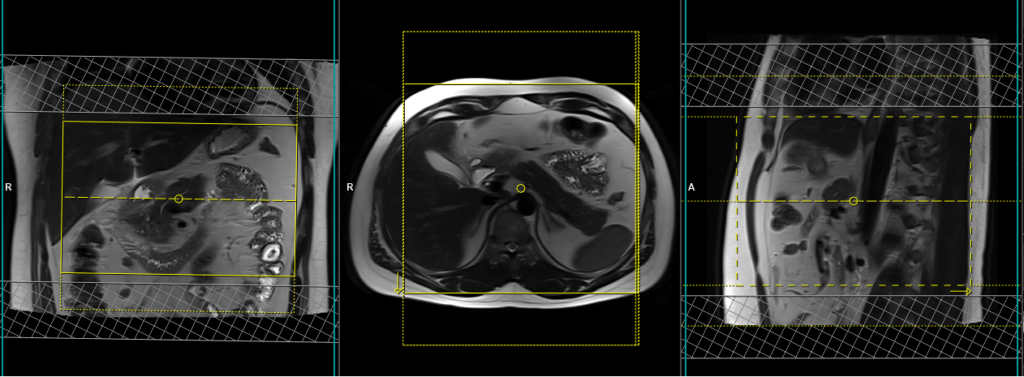

T1 VIBE dixon 3D fat sat axial breath hold dynamic 2 run post GD

Plan the axial slices on the coronal breath-hold images and position the block horizontally across the abdomen as shown. Verify the positioning in the other two planes. Establish an appropriate angle in the sagittal plane, aligning it horizontally across the abdomen. The slices must be sufficient to cover the entire pancreas, starting one inch above the pancreatic tail and extending down to the C loop of the duodenum. The phase direction should be from right to left to minimize ghosting artifacts from the anterior abdominal wall. Use phase oversampling to prevent wrap-around artifacts. Consider adding saturation bands at the top and bottom of the block to minimize artifacts caused by fat signal, arterial pulsation, and breathing. Instruct the patient to hold their breath during image acquisition.

A dynamic T1 VIBE DIXON 3D sequence comprises two VIBE 3mm 3D scans with a 15-second delay between the first and second acquisitions. The first scan captures the arterial phase, while the second scan captures the venous phase. The timing of each scan is crucial, particularly for the arterial and venous phases. A proper arterial phase acquisition should exhibit noticeable enhancement of the hepatic arteries, pancreas, and spleen, without any enhancement of the hepatic veins.

Parameters

TR 6-7 | TE 2.39 4.77 | FLIP 10 | NXA 1 | SLICE 3 MM | MATRIX 288×256 | FOV 250-280 | PHASE A>P | OVERSAMPLE 20% | BH YES |